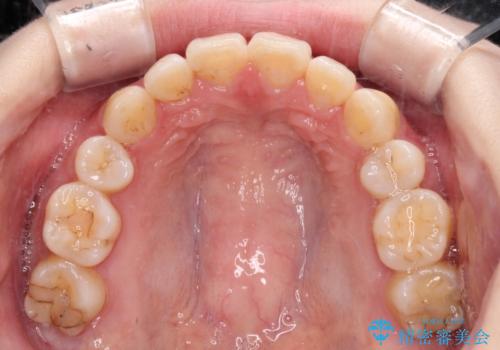

- 口元の突出感を気にして来院された患者様です。

上下左右の第一小臼歯4本を抜歯して口元を下げる治療計画としました。